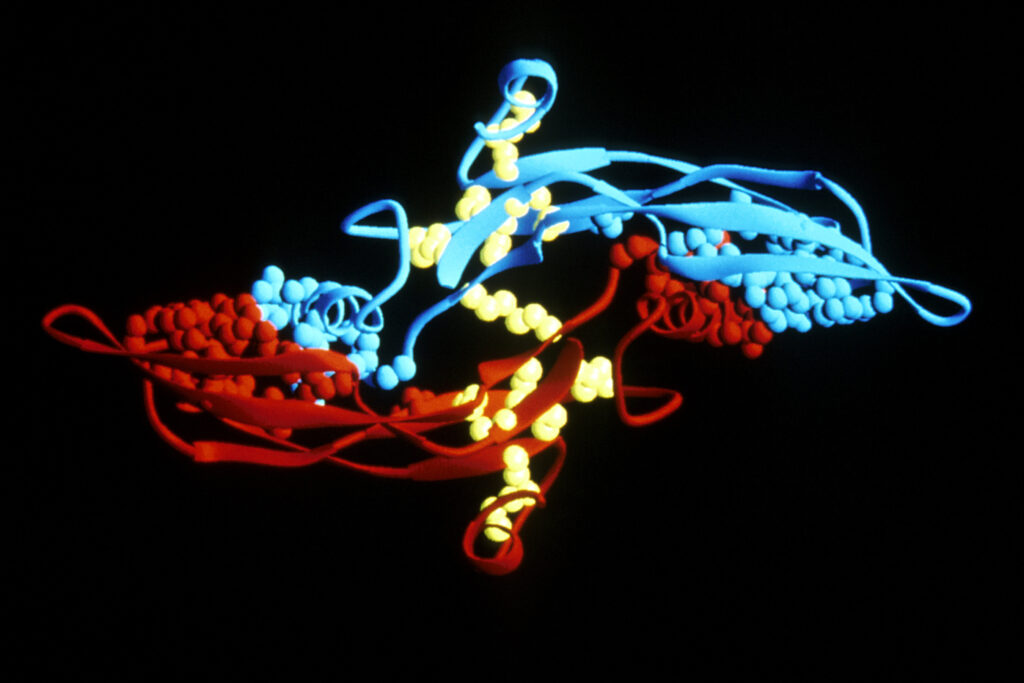

La intoxicación por bloqueadores beta-adrenérgicos es un fenómeno clínico complejo que se asocia a la administración excesiva o inadecuada de fármacos que actúan sobre los receptores beta-adrenérgicos del sistema nervioso…